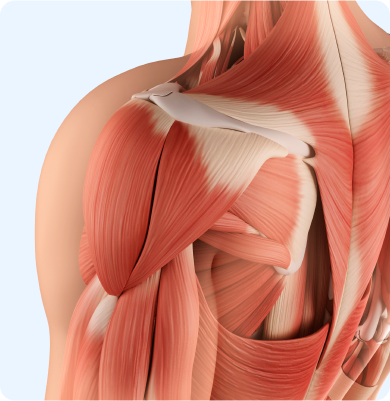

어깨 관절을 둘러싼 관절막이 퇴행성 변화를 일으키면서 염증을 유발하는 질환

주로 40~60대에 발생하며 어깨를 오래 사용하지 않거나 움직임이 제한될 때 관절이 굳어 생기거나 당뇨병 등 기저질환이 원인이 됩니다.

어깨 관절을 감싸고 있는 회전근개 힘줄이 손상되거나 찢어지는 질환

어깨를 움직일 때 어깨뼈와 힘줄이 충돌하여 염증과 통증을 유발하는 질환

팔을 반복적으로 머리 위로 들어 올리는 동작이나 잘못된 자세, 외상, 나이로 인한 퇴행성 변화 등이 원인이 됩니다.

어깨 힘줄에 칼슘이 침착되어 염증과 극심한 통증을 유발하는 질환

혈액순환 저하, 노화로 인한 퇴행성 변화, 반복적인 어깨 사용이나 충격 등이 원인이 되어 힘줄에 석회가 쌓이면서 발생합니다.

어깨 관절의 안정성을 유지해주는 연골조직인 관절와순이 손상되거나 찢어지는 질환

어깨 관절에 반복적으로 스트레스가 가해지는 스포츠 활동, 팔을 머리 위로 던지는 동작, 낙상이나 외상 등 급격한 충격 그리고 나이에 따른 조직 퇴행으로 발생합니다.

어깨 관절이 반복적으로 빠지는 상태가 습관처럼 지속되는 질환

처음 발생한 어깨 탈구 이후 관절이 불안정해지거나 선천적으로 관절이 유연한 경우, 반복적인 외상이나 스포츠 활동으로 인해 발생할 수 있습니다.

어깨 관절 내 연골이 점진적으로 닳아 없어지는 퇴행성 질환

노화에 따른 관절 연골의 퇴행, 외상, 반복적인 어깨 사용, 과거 탈구나 회전근개 파열 등이 원인이 될 수 있습니다.